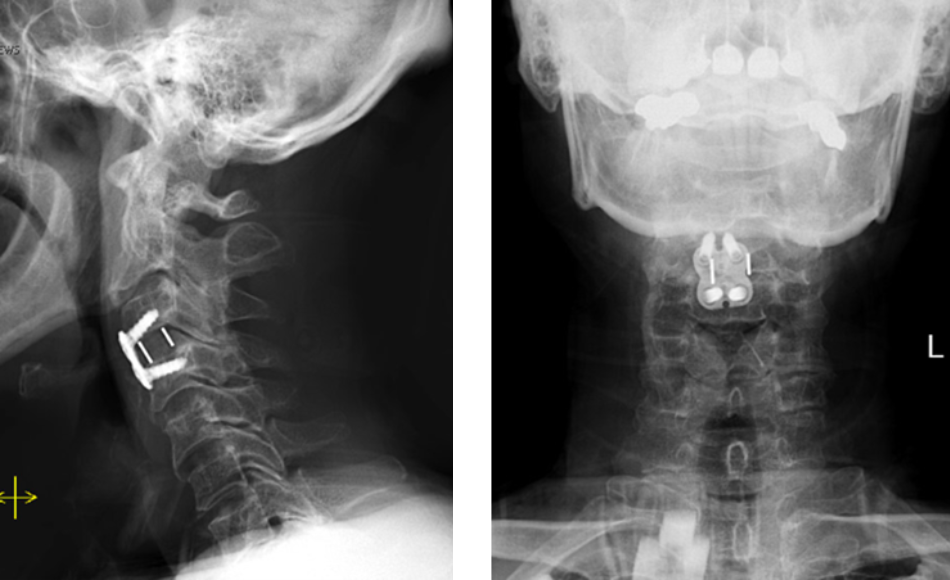

Revision Surgery Treats Intractable Neck Pain & Cervical Deformity

Author: Benjamin R. Cohen M.D., F.A.A.N.S., F.A.C.S., Read More!